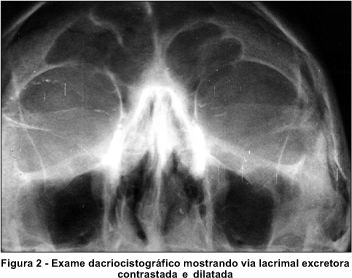

Os testes com corantes para avaliação da excreção lacrimal mostraram: teste de Milder positivo e teste de Jones I negativo bilateralmente. O paciente foi submetido a dacriocistografia (DCG) com contraste oleoso (Lipiodol) que mostrou dilatação bilateral da via lacrimal excretora, sem a presença de obstrução (Figura 2).

Os granulomas ulcerativos que ocorrem na cavidade nasal podem afetar por contigüidade as pálpebras, a conjuntiva e o ducto nasolacrimal(6). O caso relatado apresentava lesão granulomatosa na cavidade nasal, compatível histopatologicamente com leishmaniose e, provavelmente, causadora da dificuldade respiratória e do retardo de drenagem das lágrimas (Teste de Milder e Teste de Jones tipo I alterados bilateralmente, apesar do ectrópio da pálpebra inferior localizar-se apenas à direita). À DCG verificou-se passagem do corante por todo o trajeto até a cavidade nasal, porém com dilatação do ducto nasolacrimal.